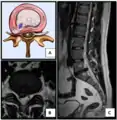

The majority of spinal disc herniations occur in the lumbar spine (95% at L4–L5 or L5–S1).[20] The second most common site is the cervical region (C5–C6, C6–C7). The thoracic region accounts for only 1–2% of cases. Herniations usually occur postero-laterally, at the points where the annulus fibrosus is relatively thin and is not reinforced by the posterior or anterior longitudinal ligament.[20] In the cervical spine, a symptomatic postero-lateral herniation between two vertebrae will impinge on the nerve which exits the spinal canal between those two vertebrae on that side.[20] So, for example, a right postero-lateral herniation of the disc between vertebrae C5 and C6 will impinge on the right C6 spinal nerve. The rest of the spinal cord, however, is oriented differently, so a symptomatic postero-lateral herniation between two vertebrae will impinge on the nerve exiting at the next intervertebral level down.[20]

Lumbar disc herniations occur in the back, most often between the fourth and fifth lumbar vertebral bodies or between the fifth and the sacrum. Here, symptoms can be felt in the lower back, buttocks, thigh, anal/genital region (via the perineal nerve), and may radiate into the foot and/or toe. The sciatic nerve is the most commonly affected nerve, causing symptoms of sciatica. The femoral nerve can also be affected and cause the patient to experience a numb, tingling feeling throughout one or both legs and even feet or a burning feeling in the hips and legs.[21] A herniation in the lumbar region often compresses the nerve root exiting at the level below the disc. Thus, a herniation of the L4–5 disc compresses the L5 nerve root, only if the herniation is posterolateral.

- Click images to see larger versions

Lumbar disc lesions, classification

Normal situation and spinal disc herniation in cervical vertebrae

Illustration depicting herniated disc and spinal nerve compression

Nucleus herniating through tear in annulus (with MRI)[8]

Illustration showing disc degeneration, prolapse, extrusion and sequestration.